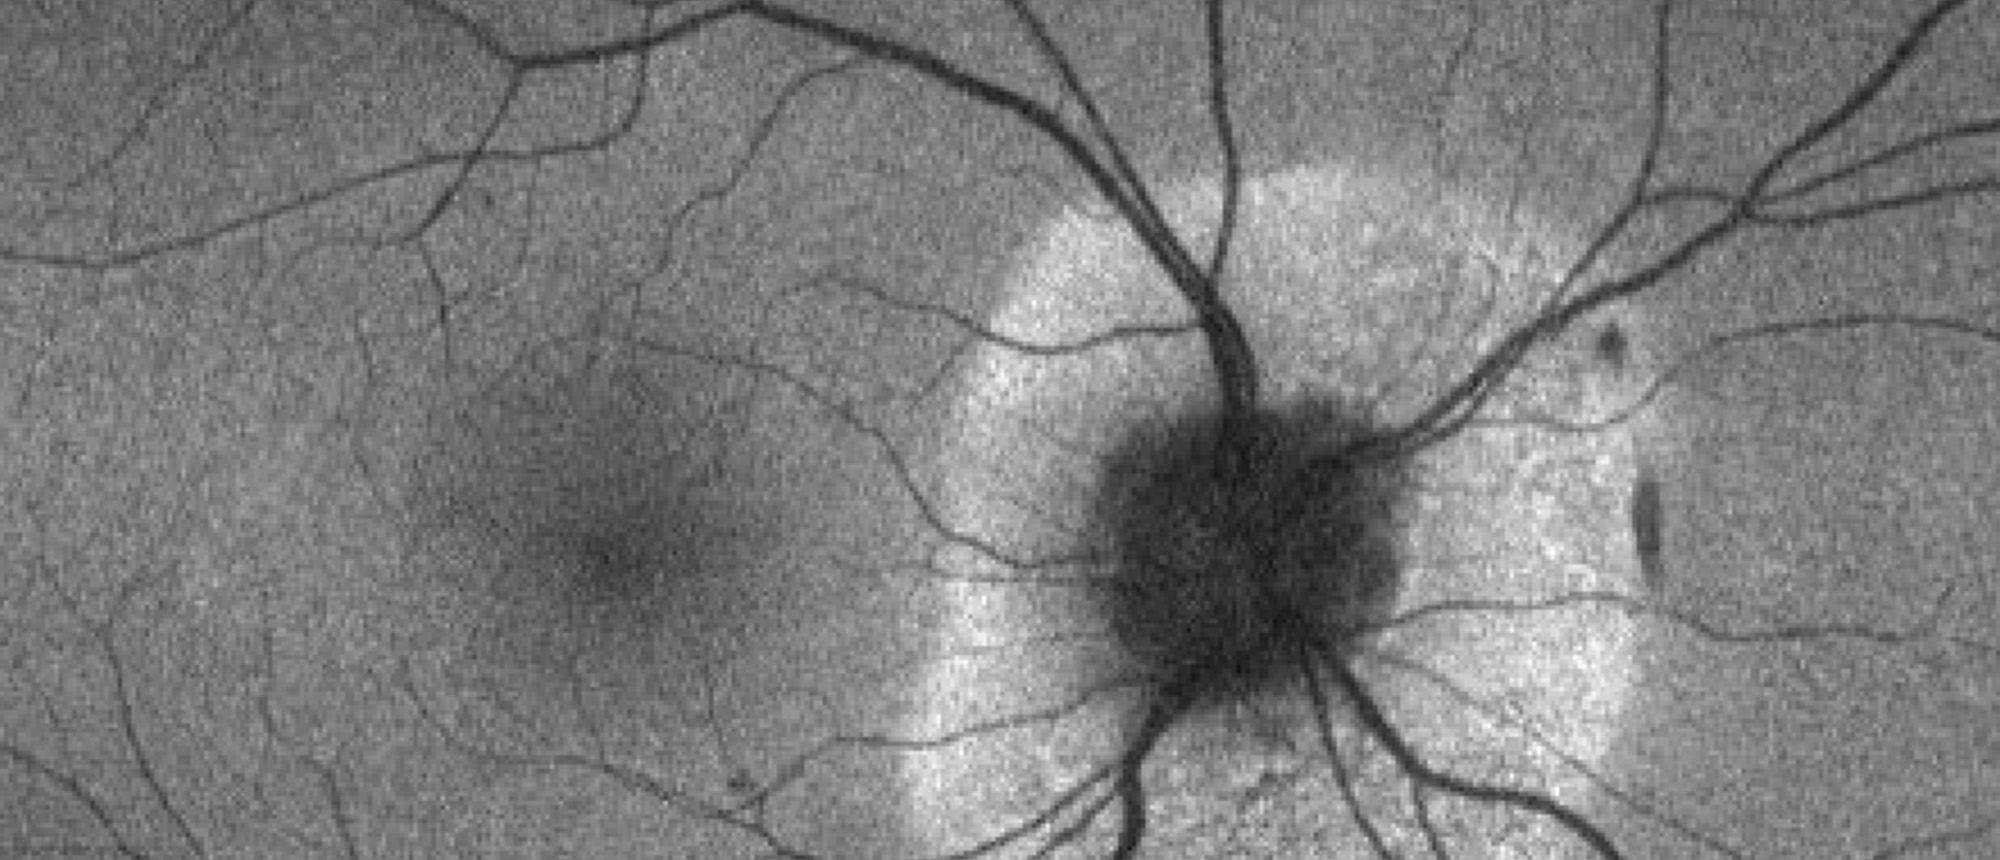

A patient discovered to have infiltrative optic neuropathy secondary to pleomorphic mantle cell lymphoma. Color fundus photo of the left eye shows grade 3 optic nerve edema with associated splinter hemorrhages as well as a few, scattered dot blot hemorrhages.